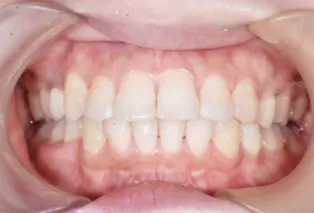

Photos intra-orales